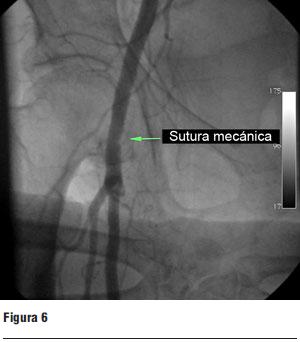

Luego del implante se retiró el introductor arterial y se cerró el orificio vascular mediante la sutura mecánica (Prostar) implantada previamente, comprobándose una hemostasis completa del sitio de abordaje (figura 6), dándose por finalizado el procedimiento.